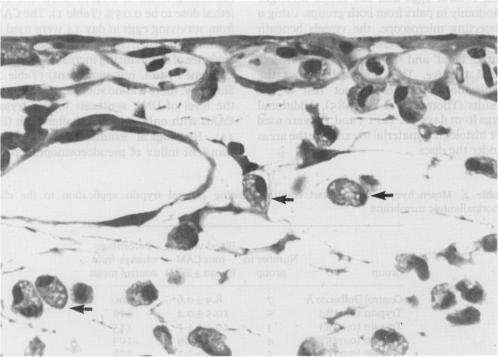

We have addressed the problem of distinguishing angiogenesis induced in the chick chorioallantoic membrane by injury and inflammation from angiogenesis induced by primary stimulation. Focal, slow-release application of trypsin stimulated a localized spoke-wheel pattern of vascularity. In comparison, a range of doses up to a sublethal amount of trypsin applied generally, in liquid form, resulted in no change in DNA synthesis or vessel content, despite a transient influx of inflammatory cells. This contrasts with previous work with fibrin degradation products, histamine and heparin which each produce characteristic patterns of increased DNA synthesis leading to angiogenesis in the entire 'dropped' area of the chorioallantoic membrane. Such general application, therefore, avoids the danger of misinterpretation of focal, toxic effects.